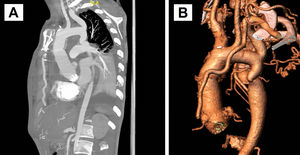

Tres meses después de la primera intervención, se realizó implante de stent cubierto aórtico de 16x58mm en zona 3-4 aórtica, con objetivo de expansión a 17mm, con apertura o «flaring» de 20mm de longitud de extremo distal a 22mm de diámetro. El abordaje fue endovascular percutáneo por arteria femoral izquierda, con colocación de catéter pigtail para control radioscópico con contraste por arteria humeral izquierda (fig. 3 A-B). El gradiente de presión arterial disminuyó a 10mmHg. La evolución postoperatoria transcurrió sin complicaciones, permitiendo el alta hospitalaria a las 48 h del implante. En la TC de control se apreciaba el stent implantado en la zona de coartación sin complicaciones, con un diámetro mínimo interno de unos 12-13mm en la zona más estrecha (fig. 3C).

A) Imagen radioscópica en la que se observa el stent cubierto aórtico de 16x58cm implantado en zona 3-4 aórtica, que se ha insertado por vía femoral, con objetivo de expansión a 17mm, con apertura o «flaring» de 20mm de longitud de extremo distal a 22mm de diámetro. También, se observa el catéter pigtail para inyección de contraste a través de la subclavia izquierda, que se ha insertado por vía humeral izquierda. B) Imagen radioscópica de resultado final con inyección de contraste a través del catéter pigtail, confirmando la correcta expansión de la zona coartada. C) Reconstrucción de la TC de aorta postimplante de stent aórtico. Se aprecia el stent implantado en la zona de coartación sin complicaciones.